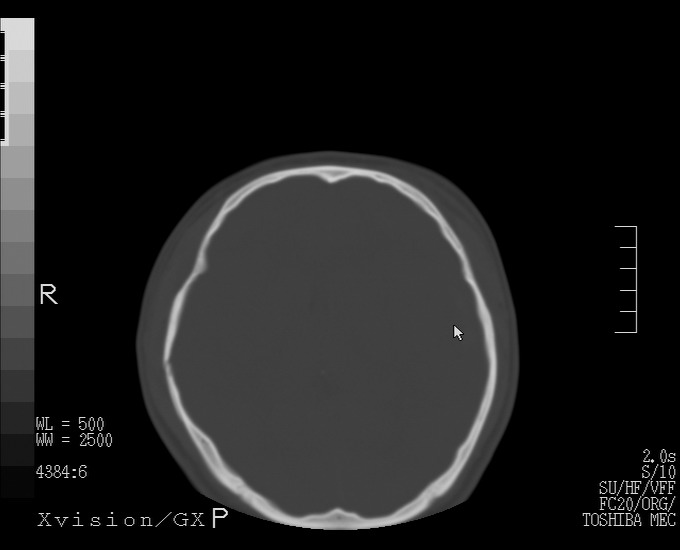

以下是引用随光逐影在2010-4-11 11:00:00的发言:[br]1)左侧额颞顶部硬膜下血肿。2)蛛网膜下腔出血。3)右侧颞顶部颅骨线形骨折。[br][br]20小时后复查:左侧额颞叶脑挫裂伤;左侧额颞顶部硬膜下血肿及蛛网膜下腔出血有吸收表现;右侧颞顶部颅骨线形骨折。[br]